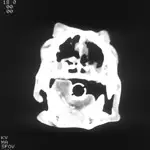

The primary differential diagnoses included nasal neoplasia and aspergillosis. No contrast-enhancing mass was seen on nasal CT, but areas of osteolysis were observed in both nasal passages and increased soft tissue opacity was seen in both frontal sinuses. The cribriform plate was intact. Rhinoscopy revealed large, irregular white plaques in both nasal passages, nasal turbinate destruction, and hemorrhage. Cytologic evaluation of a plaque confirmed fungal infection. Aspergillus fumigatus was identified both histologically and through culture.

Figure 1. Noncontrast-enhancing soft tissue densities compatible with mucus and/or blood accumulation are visible in the ventral nasal passages and frontal sinuses and were confirmed by evaluating Hounsfield values. The dog also had loss of nasal turbinates in the central nasal passages, confirmed by viewing the images with an expanded gray scale (lung window not shown). Such lung windows allow all soft tissues to be uniformly gray so that thin structures, such as turbinates, can be evaluated. (They are usually not visible in high-contrast soft tissue windows.)